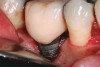

Achieving and maintaining healthy and stable peri-implant soft tissue requires the use of abutment materials that are biocompatible. This in part means using materials that have minimal affinity to bacterial colonization. Differences between titanium and zirconium abutments with regard to bacterial colonization have been of particular interest. Titanium- and zirconia-based surfaces are promptly colonized by bacterial communities similar to those found in adjacent teeth.9,16 Investigations have yielded differing results. A detailed quantitative analysis of an in vitro study found zirconia abutment surfaces have higher biofilm biomass and biofilm diversity than titanium surfaces.17 Figure 1 shows an example of an implant with a zirconia abutment with peri-implantitis.

Fig 1. Implant with zirconia abutment had peri-implantitis that led to gingival recession and exposure of the implant body.

Figure 1